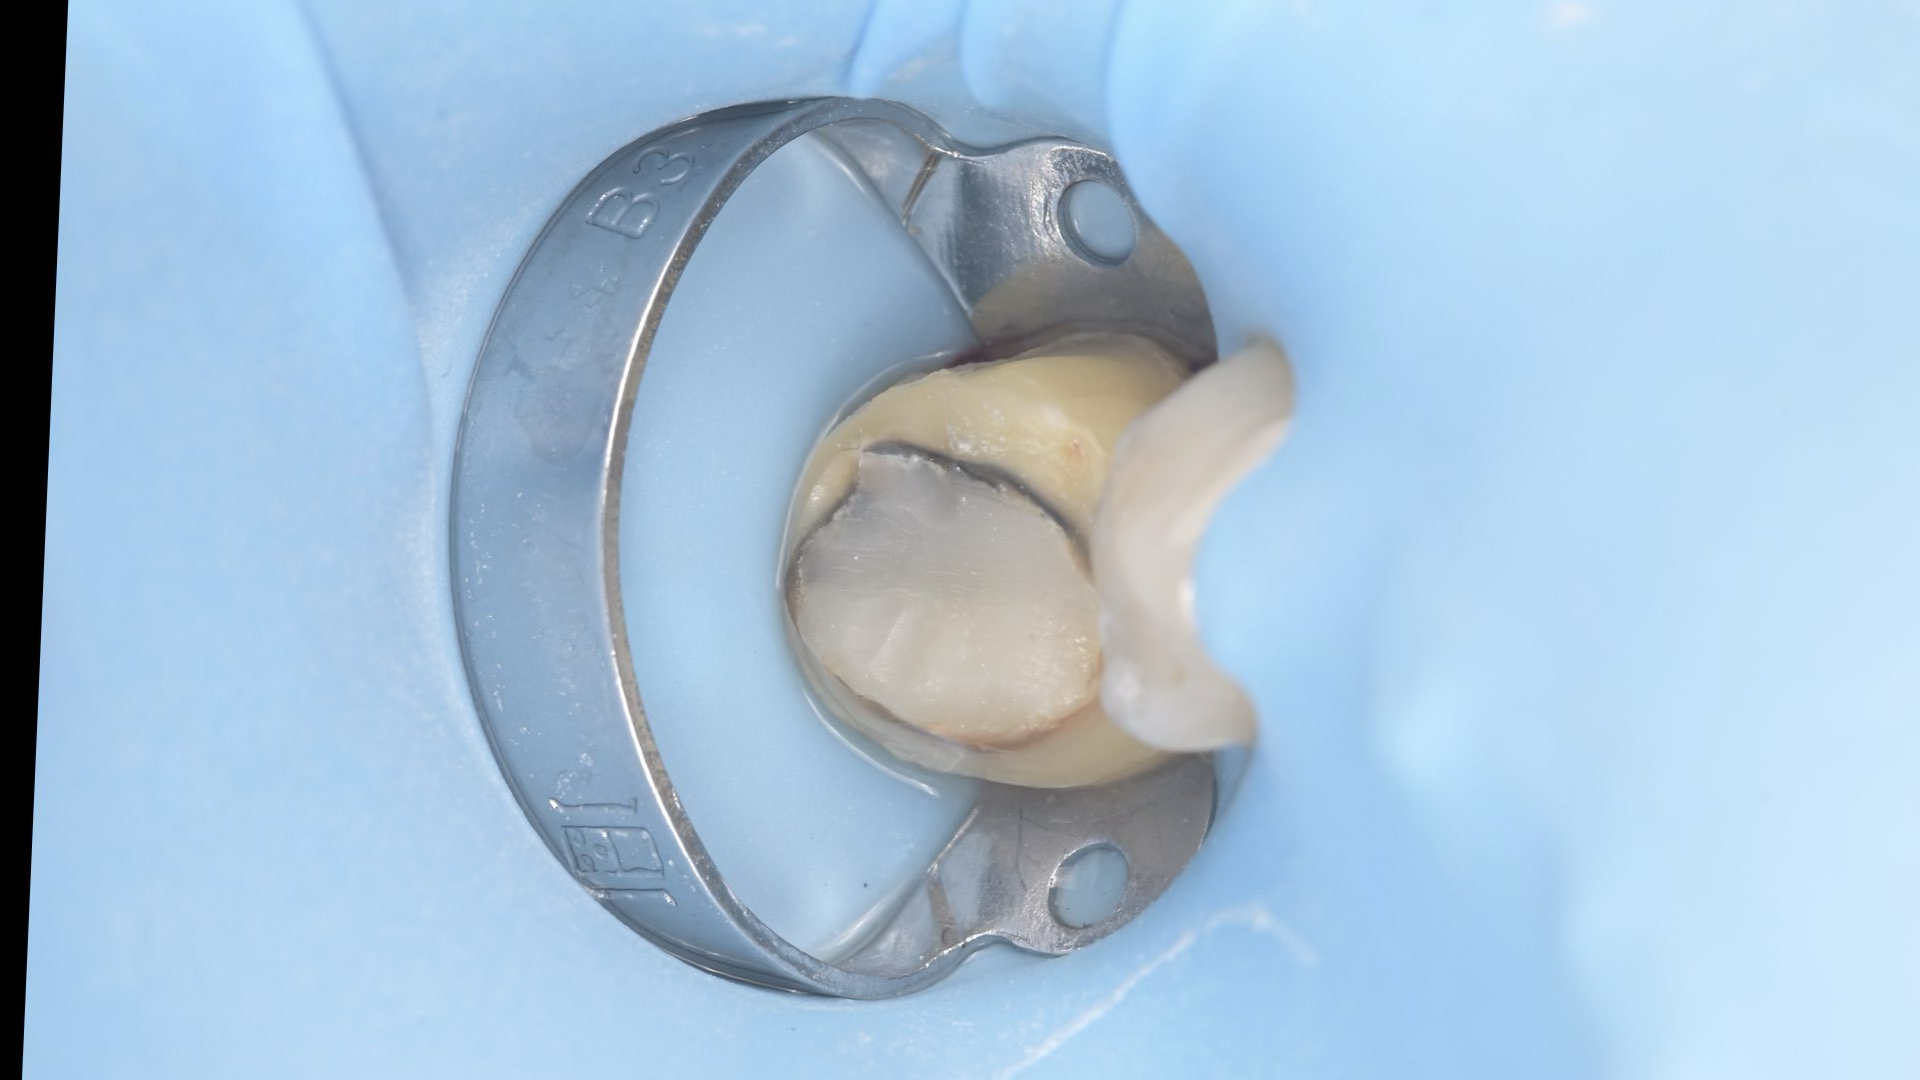

A biomimetikus fogászat egy modern megközelítés, melynek célja, hogy a fogak helyreállítását a fogorvos a természetes fog szerkezetét utánozva végezze el. A módszer kulcsa, hogy a fogat a lehető legkevésbé invazív módon kezelje, maximalizálva a megmaradt egészséges fogszövetet.

Célja, hogy az elkészült tömések és betétek (inlay, onlay) ugyanolyan erősek és rugalmasak legyenek, mint a természetes fog.

Ennek eléréséhez speciális ragasztási technikákat és bio-kompatibilis, üvegszál-erősítésű anyagokat használnak, melyek szorosan kötődnek a foghoz.

A hagyományos koronázással szemben, ahol sok ép foganyagot kell eltávolítani, a biomimetikus eljárásnál csak a sérült részeket távolítják el.

Ez segít megelőzni az úgynevezett „mély tömések” okozta gyökérkezelési szükségletet, mivel az ideg a fogban kevésbé sérül.

A megmaradó erős fogszövetnek köszönhetően a helyreállított fogak sokkal ellenállóbbak a repedésekkel és töréssel szemben.

A rágóerők egyenletesebben oszlanak el, így a fogat kevesebb stresszhatás éri rágás közben.

Ez a megközelítés hosszú távon stabilabb és tartósabb eredményt biztosít, csökkentve a jövőbeni fogászati beavatkozások szükségességét.

Összefoglalva: Az így elkészült tömések időtállóbbak, pontosabbak és jobban védik a megmaradt foganyagot, mint a hagyományos technikával elkészített tömések, a kutatások alapján, ez a jelenlegi ismereteink szerinti legmodernebb, evidence-based eljárás.